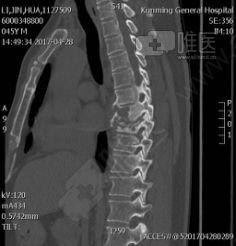

在手术之前,医生会先给你做一系列的检查,比如X光、CT、MRI等,来确定你的腰椎问题所在。同时,医生还会告诉你手术的流程、风险和注意事项。这时候,你可能会有点紧张,但别担心,医生会一直陪在你身边,给你鼓励和支持。